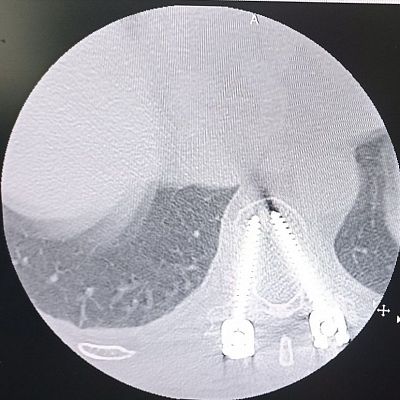

Когда мужчина стал ремонтировать свое авто, он не предполагал, что дело закончится больничной койкой. Детали, естественно, не уточним, но он без помощи домкрата решил поднять машину и… На снимке, сделанном в приемном отделении Московской областной больницы имени профессора Розанова В.Н., куда его привезли практически обездвиженного, перелом 11 грудного позвонка.

«Во время операции провели транспедикулярную фиксацию позвоночника», - рассказывает заведующая нейрохирургическим отделением Московской областной больницы имени профессора Розанова В.Н. Нина Николаевна Вознесенская https://t.me/voznesenskai_neirohirurg - Основы этой операции были разработаны в середине XX столетия - на тот момент конструкции выполнялись из нержавеющей стали. Но когда появились аппараты МРТ (магнитно-резонансной томографии), это стало огромной проблемой: с одной стороны, магнитно-резонансная томография стала одним из важнейших исследований позвоночника, а с другой - стальные фиксаторы не позволяли его проводить. Так появились титановые сплавы, которые сейчас используются».

Металлоконструкцию, которой зафиксирован позвоночник, пациент не будет чувствовать. Этот легкий титановый сплав не будет мешать движениям и не будет заметен рамкам металлоискателей. Так что при входе в официальные учреждения, метро, аэропорты и т.д. мужчине не придется носить с собой справку о том, что он был прооперирован. Эта конструкция будет видна лишь на рентгеновских снимках, на компьютерной и магнитно-резонансной томографии - ее установка не является противопоказанием для этих обследований.